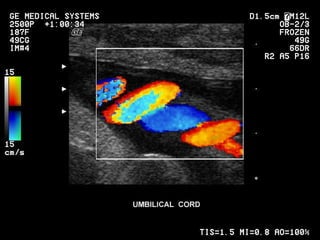

Cordão umbilical Inserção placentária. Inserção extraplacentária (velamentosa). Comprimento (40 a 60 cm). Geléia de Wharton. Artérias (2), Veia (1).

Cordão umbilical Inserçãoplacentária. Inserção extraplacentária (velamentosa). Comprimento (40 a 60 cm). Geléia de Wharton. Artérias (2), Veia (1).